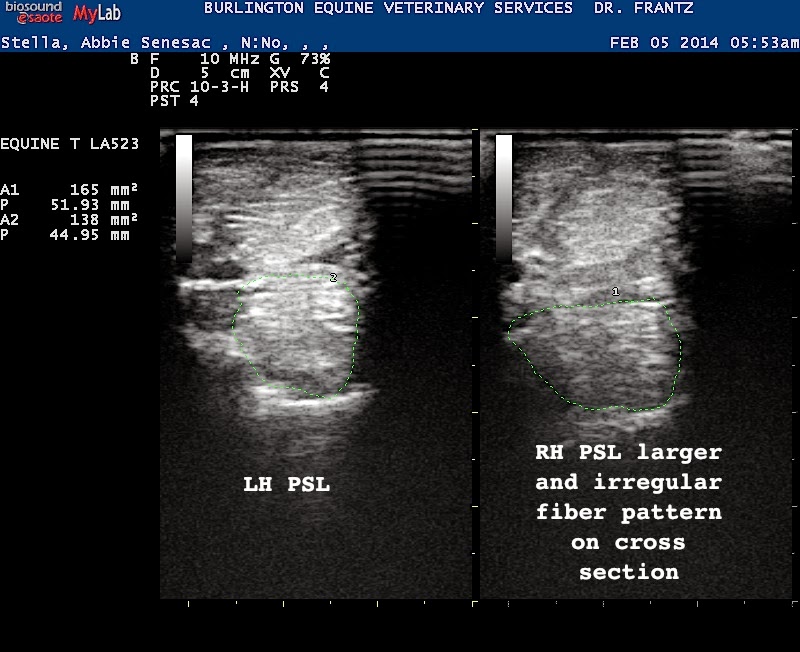

Into the Looking Glass Damage in Pictures Ultrasound What Does Glass Look Like On Ultrasound An image showing what different colors mean on an ultrasound. Left hand plain radiography demonstrated a subcutaneous foreign body medial to the 5 th metacarpal that is radiopaque, trapezoidal in shape, and measures. What do black, white and gray represent on an ultrasound? Solid tissue appears white because the outer surface reflects more sound, while fluid appears gray. It is. What Does Glass Look Like On Ultrasound.